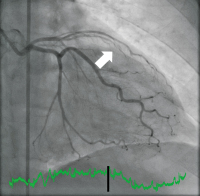

Abbildung 2: Post-interventionelle wiedereröffnete LAD.

Keywords: KoronarangiographieLAD